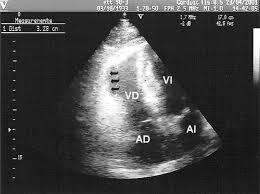

Ecocardiografía Doppler

Proporciona amplia información morfológica y funcional, pudiendo objetivar alteraciones anatómicas a nivel cardíaco, dilatación de las cavidades, arritmias, derrame pericárdico, así como obtener índices de función sistólica.